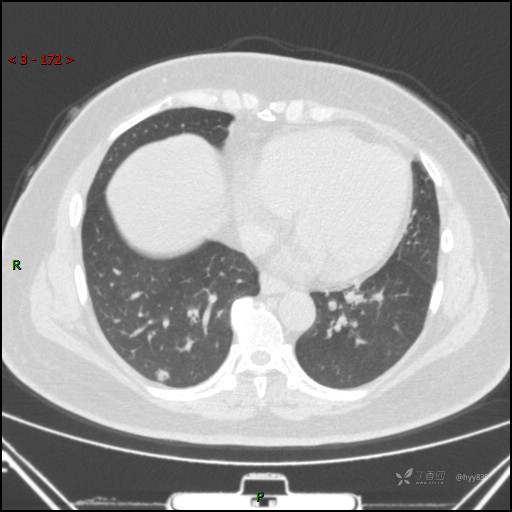

51岁/F,体检发现肺结节,又见“鬼脸”,增强也有特点,请分析---结果公布~

简要病史:体检发现右下肺结节,来我院行进一步增强检查并手术

胸部CT平扫